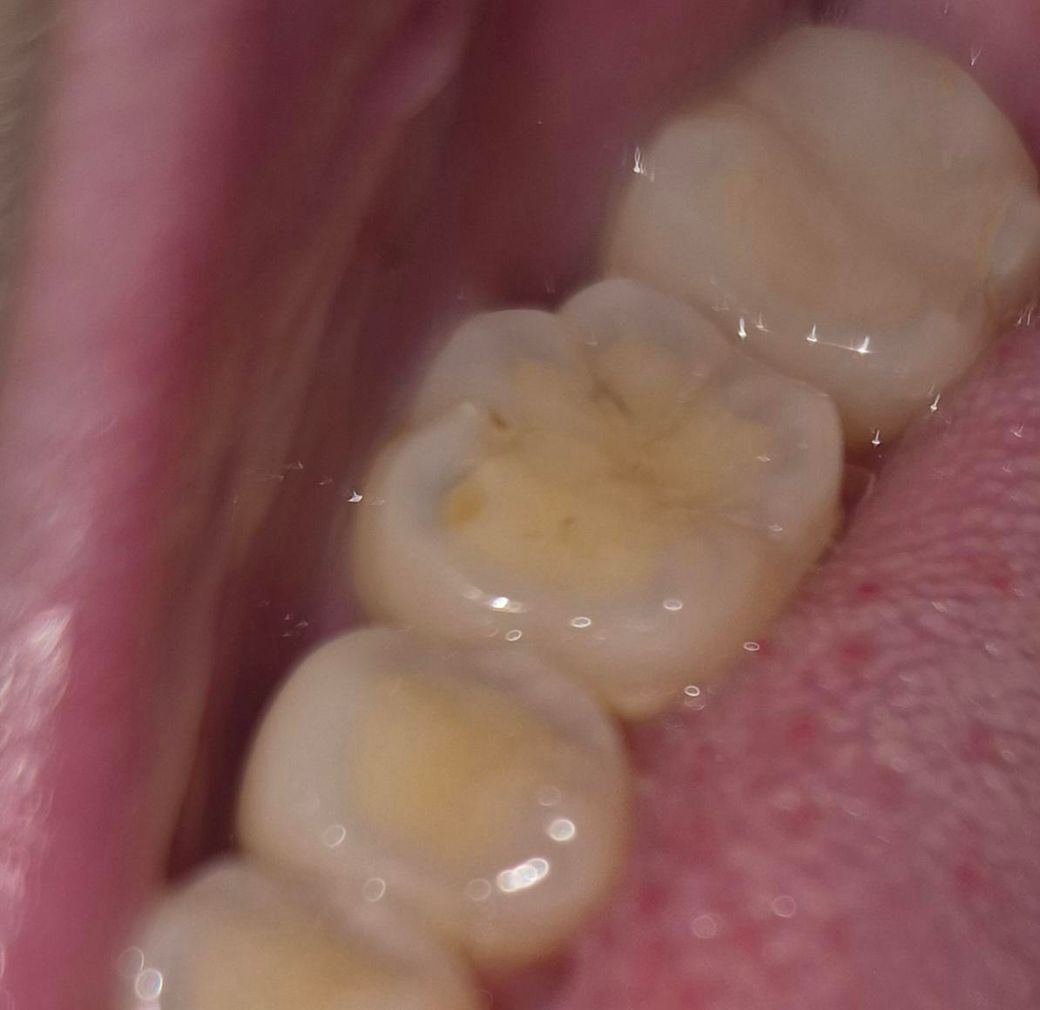

육안으로 볼 때 충치가 있어보이는데 괜찮은 걸까요?

뒤에서 2번째 어금니가 전에 크라운? 씌운 적이 있는데 이 곳에 검정색 선이 두 개쯤 보이는데 충치가 맞겠죠?

구멍이 조금 뚫려서 그런지 혀로 문지를 때 좀 시큰한 느낌이 나는데 전에 치과 갔을 때는 엄청 시린 거 아니면 나중에 다시 보자고 했거든요. 뭐 붙이기엔 구멍도 작은 데 돈 아깝다고 하셔서..

사진상으로 가장 도드라져보이는 부분은 작은 크기의 홈과 우식보다는 많이 마모된 치아 상태입니다. 이갈이 습관이 있으신지는 잘 모르겠으나 치아 교합면 마모가 상당히 있는 편으로 보이며 이에 대한 보호장치 등을 하셔야 이후에 있을 치료에도 예후가 더 좋으리라 사료됩니다.

질문하신 약간의 치아 패임 및 정지 우식정도는 경과관찰하시다가 증상 심화 시 수복 하시기를 권장드립니다.